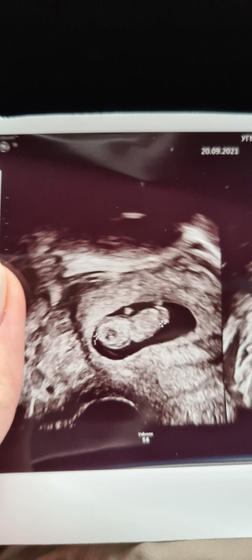

Сходила на УЗИ!!!

КТР 25мм, сердечко бьётся ?❤ ручки, ножки посмотрели… такой человечек там растёт ❤❤❤?

Блииин ну как это же это мило????Сама в пятницу была на узи на фото на любоваться не могу теперь. У мужа каждую минуту спрашиваю ну красивый же смотри какой???????.